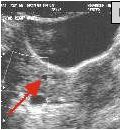

Fig. 1a-c: MRI of the L-spine (sagittal T2 weighted, coronal scout, and coronal MR Myelogram, respectively) demonstrates an incidental 4-5 cm cystic-appearing mass in the right pelvis on limited views of the pelvis. Fig. 2: a helical CT image of the pelvis, revealing a 4x5 cm low-density mass in the right hemipelvis to the right of the uterus. Fig. 3: Pelvic ultrasound shows a moderately enlarged right adnexa measuring 5 cm with low-level echoes.

IMAGING FINDINGS:  Fig. 1a-c show MRI images of the L-spine (sagittal T2 weighted, coronal scout, and coronal MR Myelogram, respectively).  They demonstrate mild scattered disc bulges and an incidental 4-5 cm cystic-appearing mass in the right pelvis on limited views of the pelvis. Incidentally, the MR Myelogram (Fig. 1c) also nicely shows the thecal sac and renal collecting systems.  Fig. 2 shows a helical CT image of the pelvis, revealing a 4x5 cm low-density mass in the right hemipelvis to the right of the uterus with CT density of about 20 Hounsfield units on pre- and post-contrast images.  A repeat transabdominal and endovaginal pelvic ultrasound with Doppler performed at AIC (Fig. 3) showed a moderately enlarged right adnexa measuring 5 cm with low-level echoes.